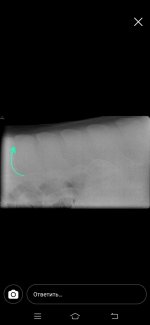

Нужна помощь. Лошадь 5 лет (6 лет будет в июне) обнаружили сегодня по ренгену спины серьезные проблемы.

По ренгену увидели что у лошади срослось костистые отростки ,образовалась хрящевая ткань. Как мне объяснили при ранней заездки лошади оказывалась не правильная работа принципе, был тяжелый всадник, не правильно подобраное седло. Из за этих факторов у лошади терлись друг об друга позвонки, произошло смещение + срастание. Как мне сказали теперь на лошади нельзя прыгать и нести верховные нагрузки. Только если будет хорошее седло +гель+меховушка ,и то если всадник не тяжелый и только (шаг, рысь, галопом в небольшом потвренмени количеству). В чем суть вопроса кто то может посоветовать подкормки или что то подобное

Как мне сказали это ничем не исправить уже...но можно что нибудь давать для поддержания формы или колоть (а вот что не сказали т.к. Врачи не специализировался именно на этом) есть ли тут ветеринары? Позже могу прикрепить снимки (когда скинут мне их на почту) спасибо всем заранее

По ренгену увидели что у лошади срослось костистые отростки ,образовалась хрящевая ткань. Как мне объяснили при ранней заездки лошади оказывалась не правильная работа принципе, был тяжелый всадник, не правильно подобраное седло. Из за этих факторов у лошади терлись друг об друга позвонки, произошло смещение + срастание. Как мне сказали теперь на лошади нельзя прыгать и нести верховные нагрузки. Только если будет хорошее седло +гель+меховушка ,и то если всадник не тяжелый и только (шаг, рысь, галопом в небольшом потвренмени количеству). В чем суть вопроса кто то может посоветовать подкормки или что то подобное

Как мне сказали это ничем не исправить уже...но можно что нибудь давать для поддержания формы или колоть (а вот что не сказали т.к. Врачи не специализировался именно на этом) есть ли тут ветеринары? Позже могу прикрепить снимки (когда скинут мне их на почту) спасибо всем заранее